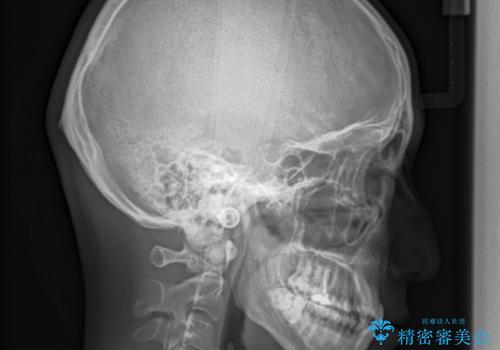

ガタガタの歯並び、八重歯をなおしたい、骨格性下顎前突 カモフラージュ矯正

骨格的に上顎骨が小さいために相対的に下顎骨が前に出ていたため、歯の傾きなど理想的な仕上がりが難しく、外科矯正ではなく歯列矯正の場合はカモフラージュ矯正になること説明の上、矯正治療を進めることになりました。